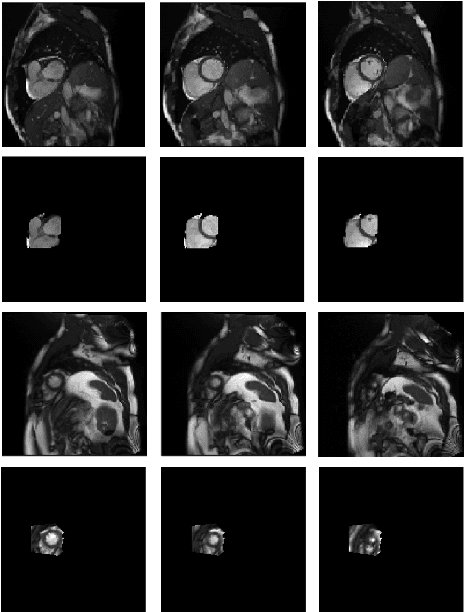

Abstract:Population imaging studies rely upon good quality medical imagery before downstream image quantification. This study provides an automated approach to assess image quality from cardiovascular magnetic resonance (CMR) imaging at scale. We identify four common CMR imaging artefacts, including respiratory motion, cardiac motion, Gibbs ringing, and aliasing. The model can deal with images acquired in different views, including two, three, and four-chamber long-axis and short-axis cine CMR images. Two deep learning-based models in spatial and frequency domains are proposed. Besides recognising these artefacts, the proposed models are suitable to the common challenges of not having access to data labels. An unsupervised domain adaptation method and a Fourier-based convolutional neural network are proposed to overcome these challenges. We show that the proposed models reliably allow for CMR image quality assessment. The accuracies obtained for the spatial model in supervised and weakly supervised learning are 99.41+0.24 and 96.37+0.66 for the UK Biobank dataset, respectively. Using unsupervised domain adaptation can somewhat overcome the challenge of not having access to the data labels. The maximum achieved domain gap coverage in unsupervised domain adaptation is 16.86%. Domain adaptation can significantly improve a 5-class classification task and deal with considerable domain shift without data labels. Increasing the speed of training and testing can be achieved with the proposed model in the frequency domain. The frequency-domain model can achieve the same accuracy yet 1.548 times faster than the spatial model. This model can also be used directly on k-space data, and there is no need for image reconstruction.